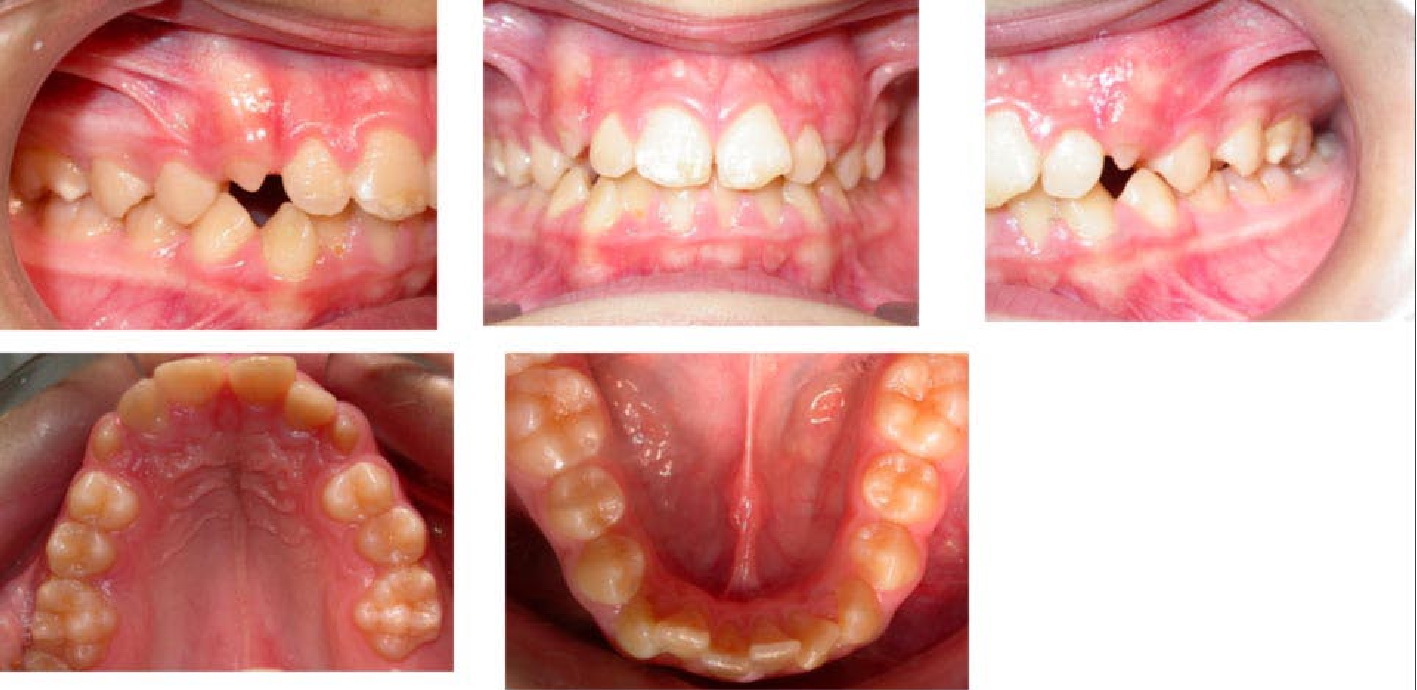

Pediatric & Adolescent Orthodontics

Early intervention can guide jaw growth and prevent future complications.

You will learn about:

- Growth monitoring

- Space maintainers and expanders

- Phase I and Phase II treatment

- Communication strategies for younger patients

- Parental education

Orthodontic assistants must understand both clinical mechanics and patient psychology.